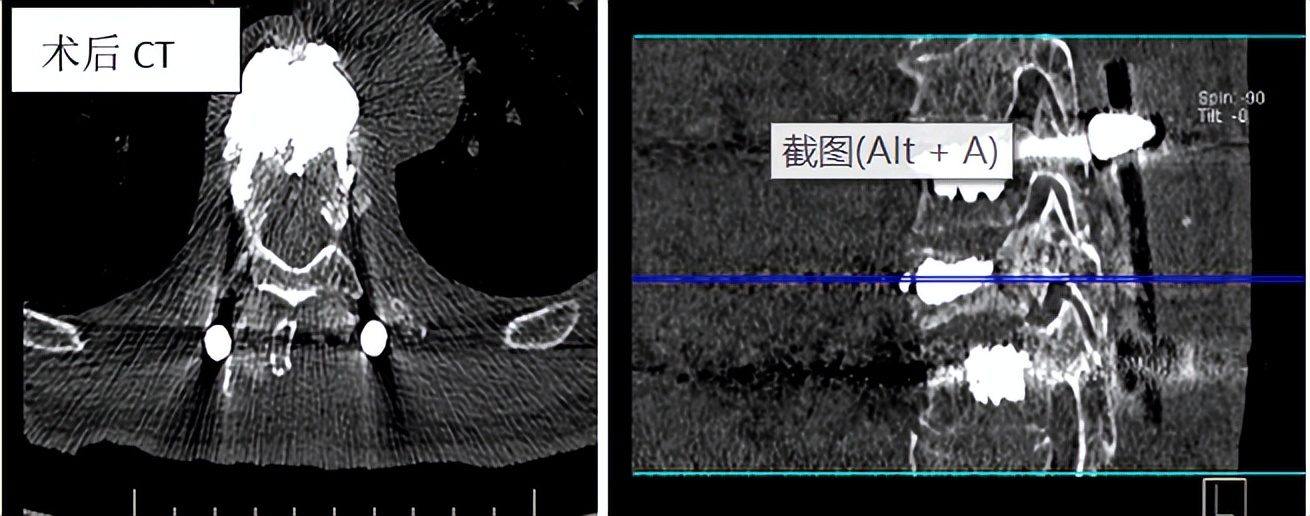

椎弓根钉-棒系统内固定 :主要适用于严重后凸畸形需要截除椎骨矫正,椎体后缘骨块碎裂后压迫脊髓,神经损伤症状、体征显著,以及不稳定椎体骨折患者。

※开放手术治疗 :切开复位、经椎弓根螺钉内固定术,复位效果较好,可以矫正后凸畸形并增强脊柱稳定性。但手术创伤相对较大,恢复相对较慢。